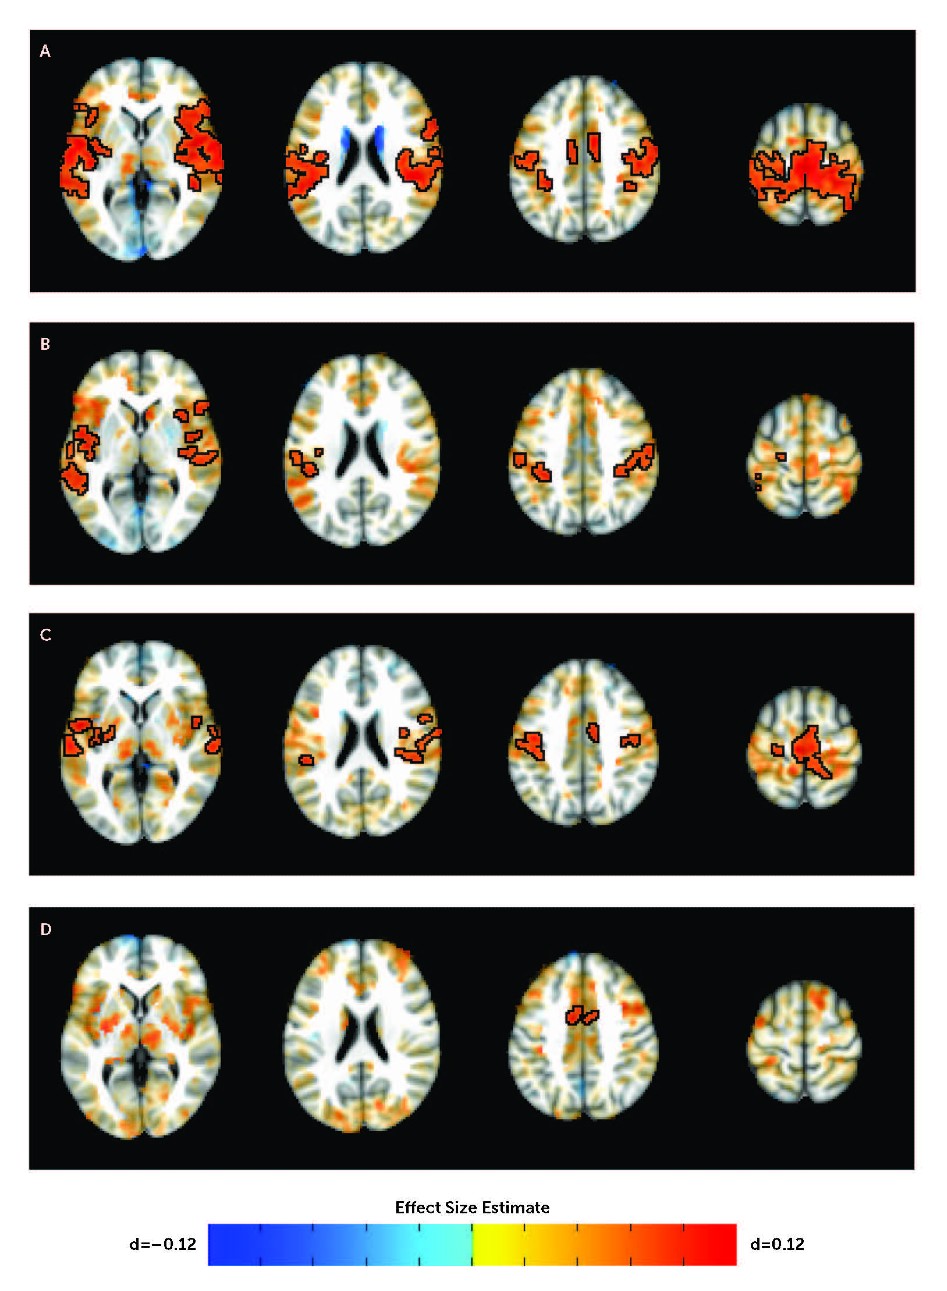

They found that youth with ADHD had heightened connectivity between structures deep in the brain involved in learning, movement, reward, and emotion (caudate, putamen, and nucleus accumbens seeds) and structures in the frontal area of the brain involved in attention and control of unwanted behaviors (superior temporal gyri, insula, inferior parietal lobe, and inferior frontal gyri).